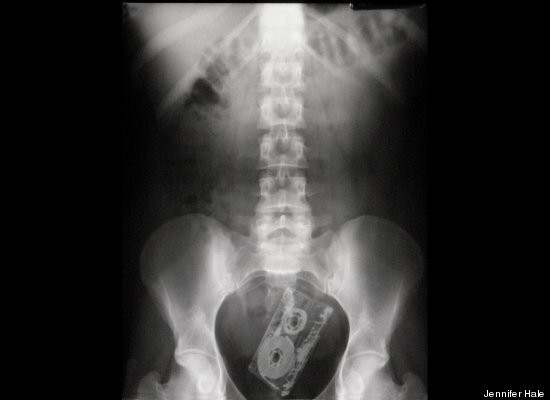

Sindhian nảy ra ý tưởng về những “chuyện lạ” này khi điều trị cho một bệnh nhân cấp cứu vài năm trước và nhìn thấy một cuốn băng cát-xét trong bản chụp X-quang.

Đừng nghĩ rằng người ta chỉ dễ bị hóc với những vật nhỏ, bác sĩ Sindhian đã từng cấp cứu cho một bệnh nhân bị kẹt cuộn băng cát-xét trong bụng.